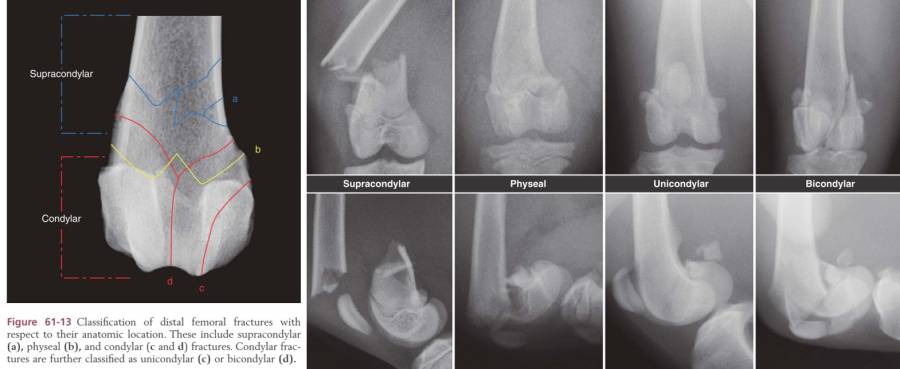

distale Femurfrakturen